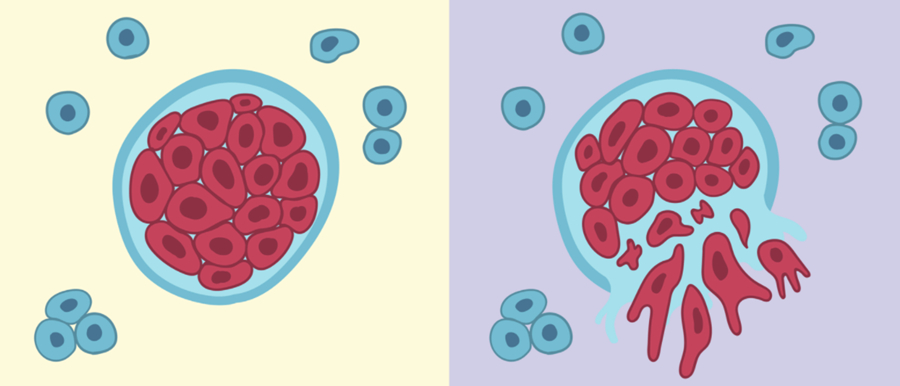

第二个问题——癌症和肿瘤有区别吗?肿瘤分为良性肿瘤和恶性肿瘤,其中恶性肿瘤又称癌症。

我给大家看两个图(内容或会引起不适,请自行观看文前视频),左边这是一个小伙子,腿上长了一个120公斤的肿瘤,右边是一个PET-CT,可以看到,上面的黑点基本都是癌细胞,已经布满了这个人全身,请问,哪个是良性的,哪个是恶性的?没错,左边这个是良性肿瘤,右边那个是恶性肿瘤,良性和恶性区别是什么?简单的说,最大的区别就是有没有扩散转移。良性肿瘤一般有一个比较完整的包膜,它就在那趴着,不会到处跑,去干坏事;而恶性肿瘤有转移,有的恶性肿瘤,你甚至都找不到它的原发灶在哪里,但是他身上到处都是,这就是良性和恶性的区别。

首先,植物是肯定会得肿瘤的,比如,在美国就有专门一群人,他们的职业就是去树林里面找树瘤,割下来,做成观赏艺术品。但是如果我们定义癌症是可以转移的肿瘤,植物是没有癌症的。植物没有能转移的癌症有两个原因,第一个是它有细胞壁,每一个细胞像砖块一样摞在一起,所以它不像动物的细胞能够到处跑;第二,人身上有血液循环系统和淋巴循环系统,很多癌细胞就是通过这些系统来转移的,而植物没有血液系统和淋巴系统,植物的循环系统只循环水和无机盐,不会有细胞在里面到处跑,这两个原因使得植物没有能够转移的癌症。

所以,癌症发生的前提除了它自己变成一个坏细胞,它必须要实现一个步骤叫做免疫逃逸。癌细胞和免疫系统其实是在持续的互相进化,互相碰撞中,它们之间的相互关系可以描述成三个阶段,第一个阶段叫做免疫清除,这时免疫细胞占绝对优势,只要有一个坏细胞就杀死,第二个阶段叫做免疫平衡,这个时候癌细胞又进化了,它没那么容易能被免疫系统清除,但是免疫系统也没有强大到能够把所有的癌细胞都干掉,癌细胞已经可以短期的、甚至长期的存活下来,免疫平衡可能会持续几十年。第三个才是免疫逃逸阶段,这个时候癌细胞已经完全逃脱免疫系统的监管,它能够到处溜达、繁殖,变成了恶性的癌症。所以当大家发现临床上出现恶性肿瘤的时候,就是免疫逃逸的阶段,之所以说癌症是一个老年病,就是因为免疫逃逸这个过程,再加上前面突变的积累过程,可能要几十年,所以一般来说人要到比较老的时候,癌症出现的概率会更大一些。